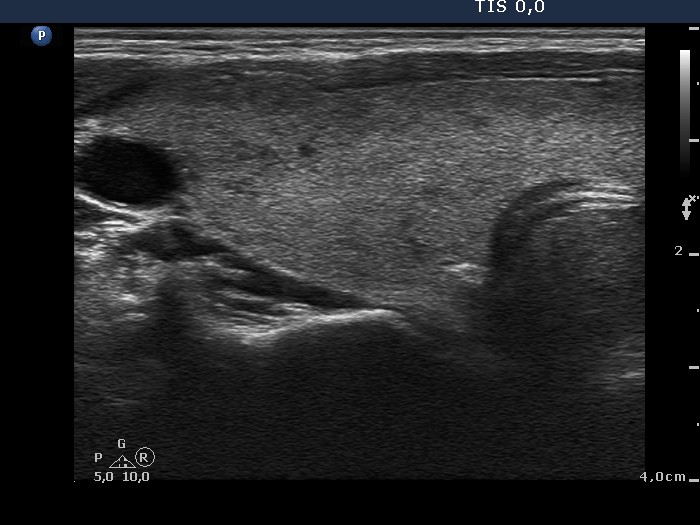

Follow-up investigation 40 months after first visit (ultrasonographic picture 1)

Patient on daily 5 mg methimazole therapy in hypothyroid state

Right lobe, transverse scan. The echogenicity of the thyroid became normal, while the thyroid has increased compared with the previous investigation. This enlargement is the consequence of the TSH elevation.